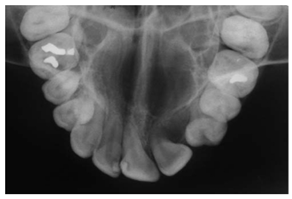

| Occlusal X-ray | N.A | Detecting abnormal, extra teeth, jaw fractures, a cleft palate, cysts and abscesses | ![]() | Displaying a section or entire arch of teeth in the upper or lower jaw |